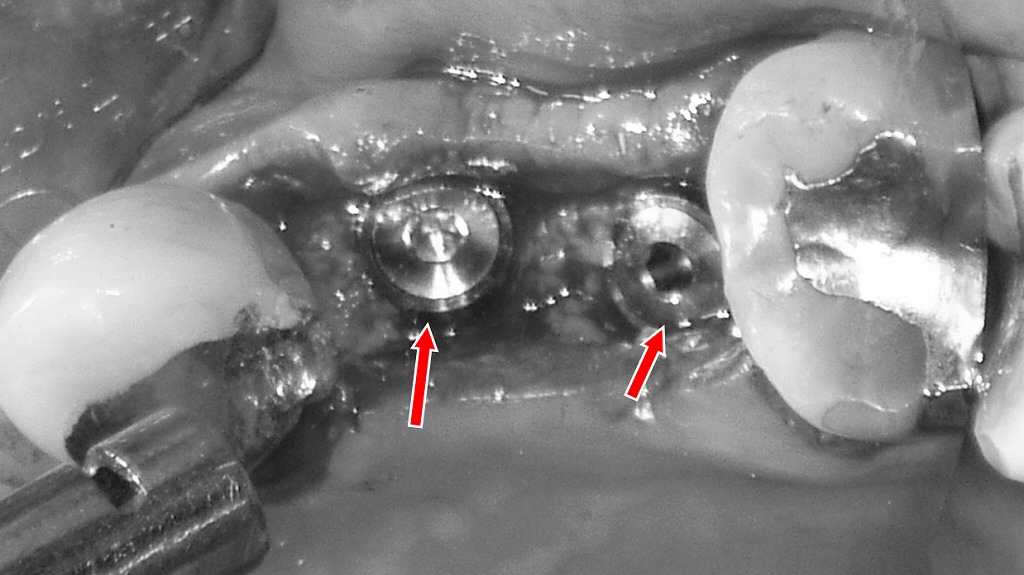

上顎4番・5番が欠損した部位に対し、インプラント治療で歯の機能回復を行った症例です。欠損状態では噛み合わせの乱れや骨吸収が進行する可能性がありますが、インプラント埋入により人工歯根を確実に固定し、周囲の歯を削らずに本来の噛む力を取り戻すことができます。術中写真では、適切な位置に埋入されたインプラント体が確認でき、今後は骨と結合することで安定した土台となり、最終的な被せ物で自然な咬合と見た目を回復していきます。